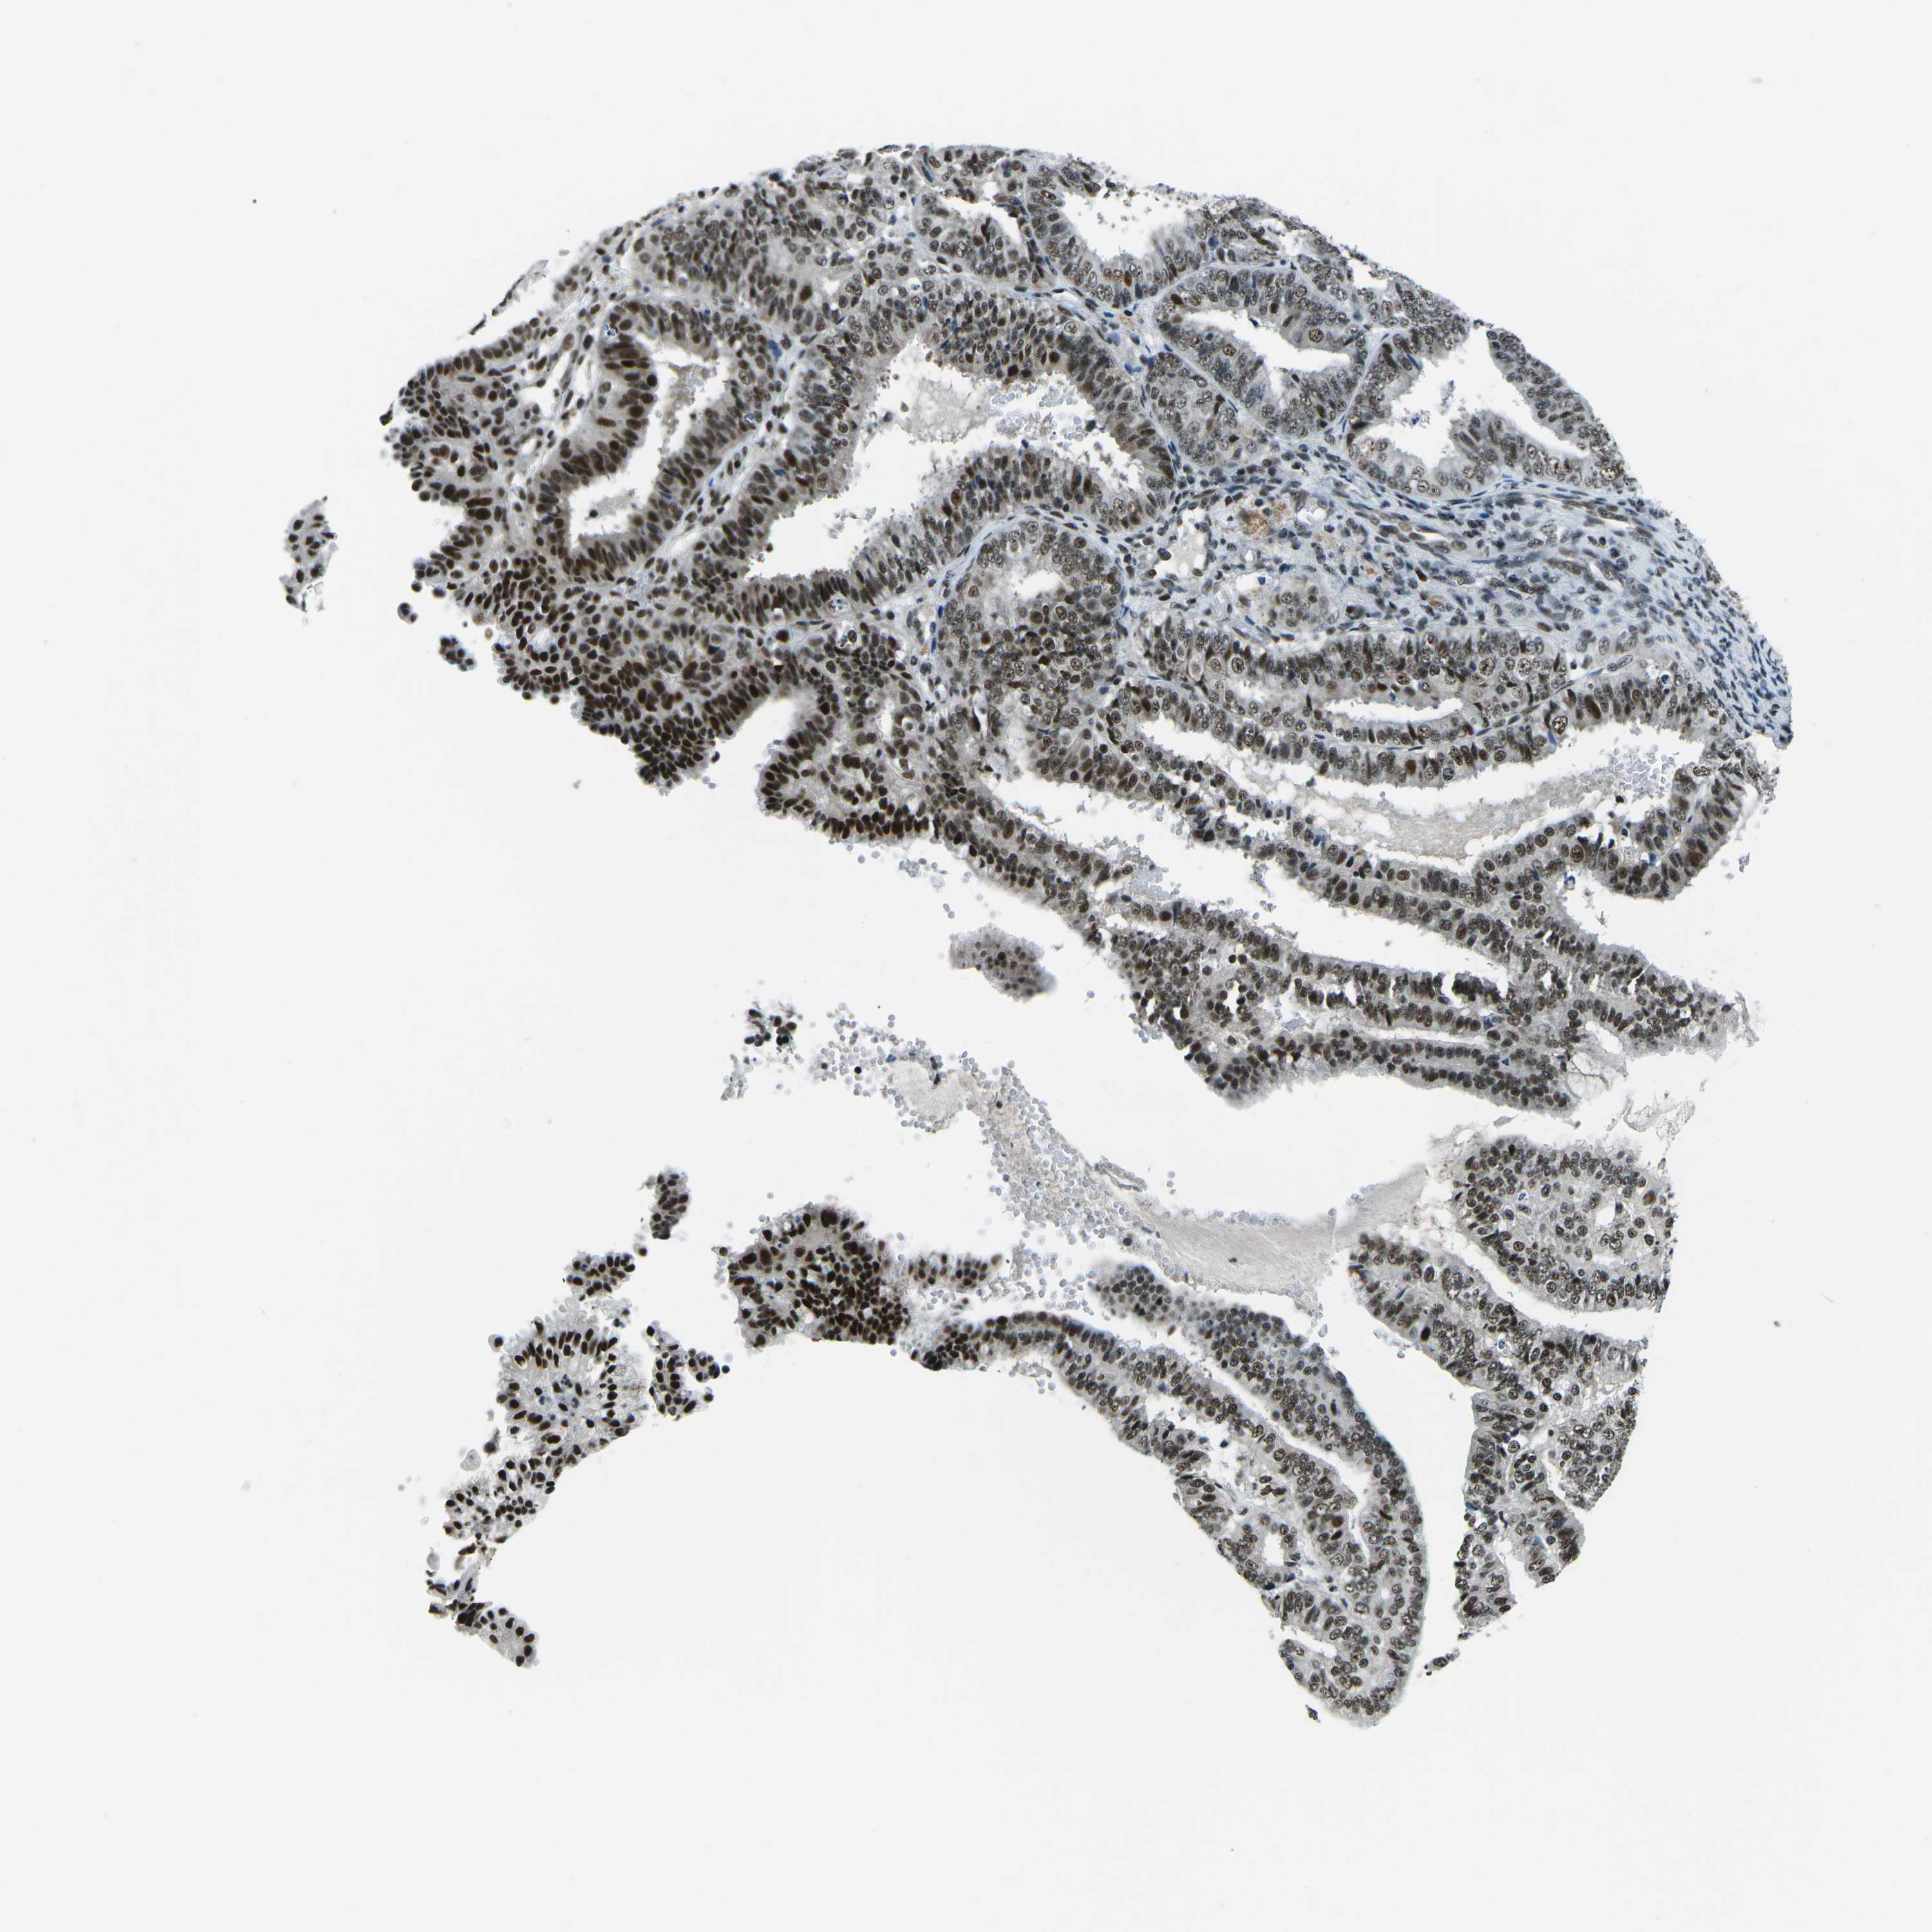

ENDOMETRIAL CANCER - Protein expressioni

A mouse-over function shows sample information and annotation data. Click on an image to view it in a full screen mode. Samples can be filtered based on level of antibody staining by selecting one or several of the following categories: high, medium, low and not detected. The assay and annotation is described here.

Note that samples used for immunohistochemistry by the Human Protein Atlas do not correspond to samples in the TCGA dataset.

Antibody stainingi

Antibody staining in the annotated cell types in the current human tissue is reported as not detected, low, medium, or high, based on conventional immunohistochemistry profiling in selected tissues. This score is based on the combination of the staining intensity and fraction of stained cells.

Each image is clickable and will lead to virtual microscopy that enables deeper exploration of all samples and also displays staining intensity scores, fraction scores and subcellular localization as well as patient and tissue information for each sample.

Antibody HPA019703

Antibody CAB016547

Staining

High

Medium

Low

Not detected

Intensity

Strong

Moderate

Weak

Negative

Quantity

>75%

75%-25%

<25%

None

Location

Nuclear

Cytoplasmic/membranous

Cytoplasmic/membranous,nuclear

Adenocarcinoma, NOS

Adenoma, NOS